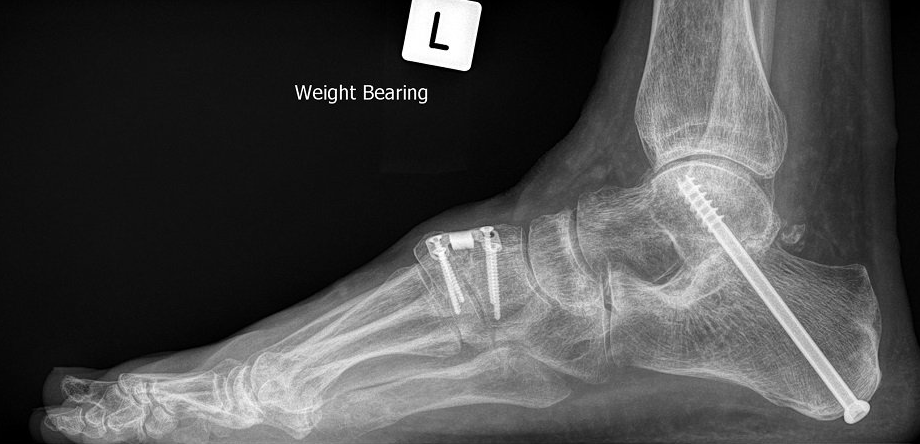

Flat foot surgery in adults is a multi-level procedure

aiming to simultaneously correct calf tightness, bone alignment, joint stability and tendon function.

- spring ligament repair vs sinus tarsi implant

- calcaneal osteotomy vs hindfoot fusion

- Cotton osteotomy vs midfoot fusion.